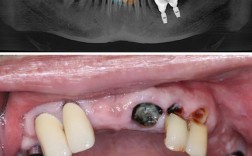

通过CBCT、全景片等影像学检查,精确测量牙槽骨的高度、宽度、密度,判断骨缺损范围,制定植骨方案,同时检查患者全身健康状况(如是否有糖尿病、高血压等),排除手术禁忌。

当牙槽骨骨量不足时,骨粉是种牙的“必要材料”,以下几种情况常见于需要骨粉的患者:

缺牙时间过长,骨吸收严重

牙齿缺失后,牙槽骨缺乏咀嚼刺激,会逐渐萎缩,缺牙后3个月开始出现骨吸收,1年后吸收速度减缓,但长期缺牙可能导致牙槽骨高度和宽度明显不足,后牙区承担主要咀嚼功能,缺牙后骨吸收更快,可能需要大量骨粉填充。

牙周病导致的骨缺损

牙周病是牙齿松动的“隐形杀手”,长期炎症会破坏牙槽骨,导致骨组织吸收、甚至形成“骨下袋”,这类患者种牙前,通常需要先治疗牙周病,再通过植骨恢复骨量。